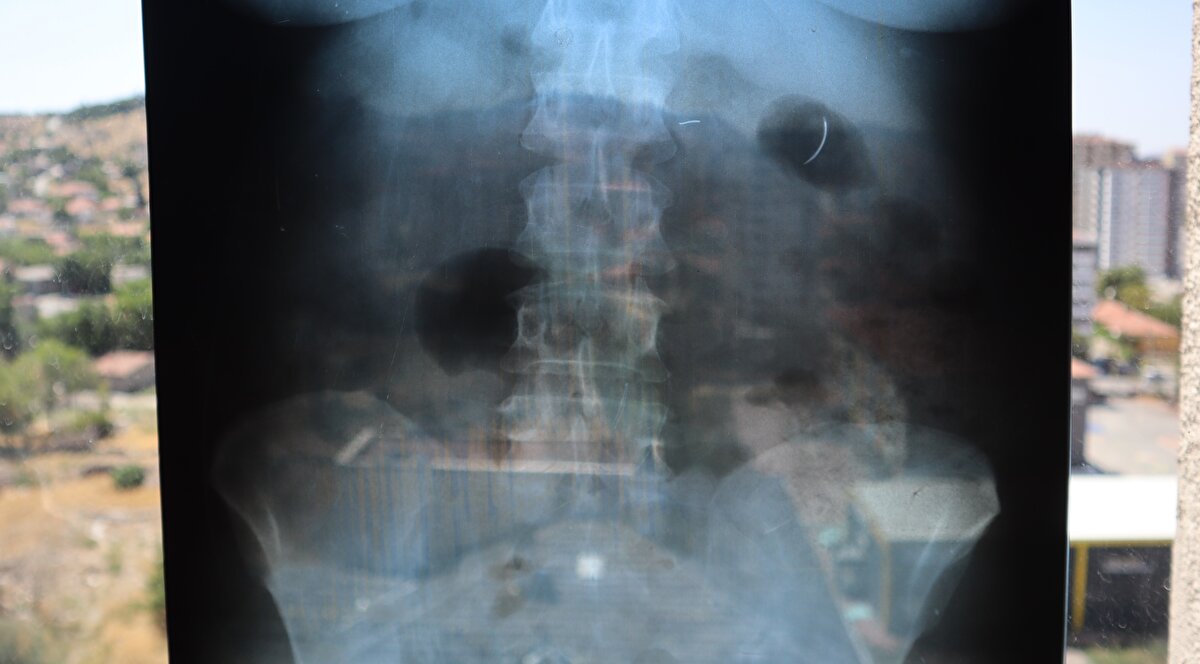

Kentte yaşayan 2 çocuk annesi Ayhan Tanyıldız, 2003 yılında karaciğerindeki kist nedeniyle ameliyat oldu. Ameliyat olduktan 6 yıl sonra böbrek rahatsızlığı nedeniyle hastaneye giden Tanyıldız’ın çekilen röntgeninde iğne görüldü. Tanyıldız’ın kist ameliyatı sırasında karnında ameliyat iğnesi unutulduğu ortaya çıktı.

Kendisini özel hastanede ameliyat eden Genel Cerrahi Doktoru İ.D.’ye dava açan Tanyıldız, ağrılarının nedeninin karnında unutulan ameliyat iğnesi olduğunu öğrendi. 19 yıl sonra mahkemesi de sonuçlanan Tanyıldız, bir miktar tazminat almaya hak kazandı. 22 yıldır ameliyat iğnesiyle yaşayan Tanyıldız, “2003 yılında ameliyatım yapıldı. Karaciğerimdeki kistten dolayı ameliyat oldum. Karaciğerimde kist oluşmuş. Kisti alırken ameliyat iğnesini unutmuşlar. 6 yıl sonra fark ettim. İlk öğrendiğimde başka doktora gittim, böbreklerimden rahatsızlanmıştım. Doktor film çekince ‘sen MR’a girme, ciğerinde iğne var’ dedi. O zaman fark ettim. Fiziksel olarak hala ağrısını, yıllardır çekiyorum” diye konuştu.